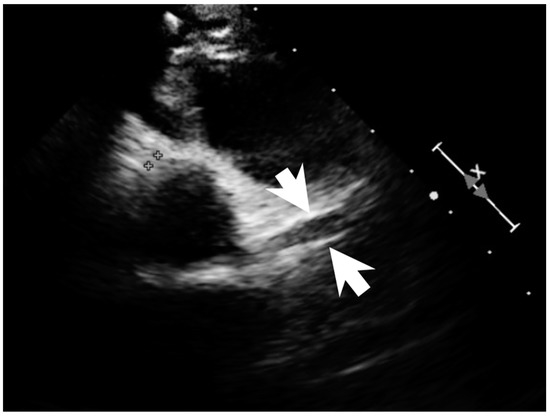

2. Case Report